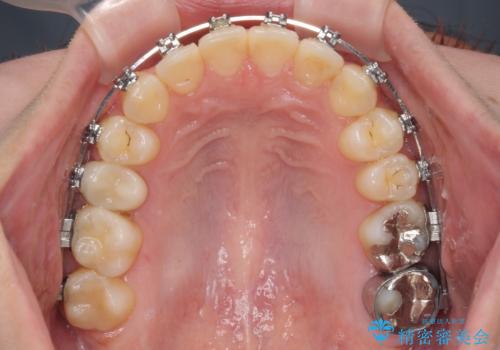

- 矯正装置

- メタルブラケット

マウスピース矯正では前歯の神経への負担が大きいことを懸念され、ワイヤー装置による矯正治療を行うこととしました。

クロスバイトが改善する際は、前歯しか接触しないため、痛みがあったり食事が取りにくかったりと、不便な時期がありますが、1年強の短期間で無事に治療を終えることができました。